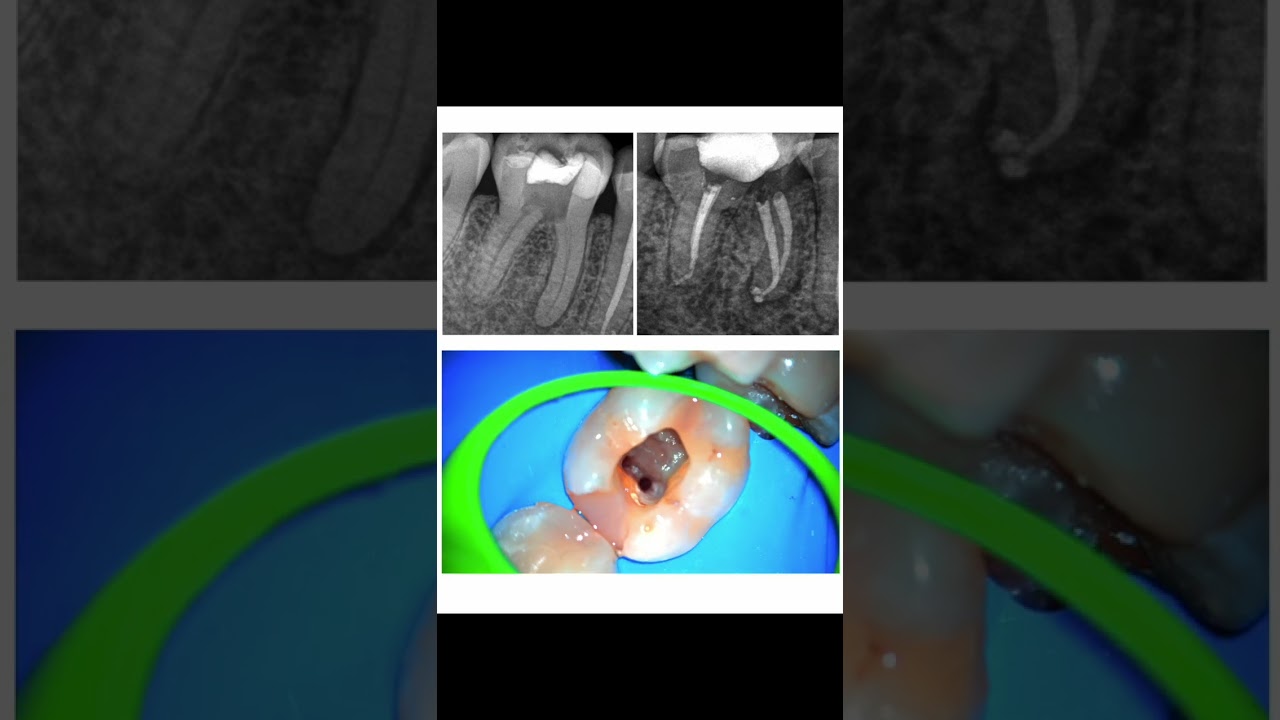

Conductos calcificados - ADA REC

El Dr. Pedro Barreiro nos habla de los conductos calcificados y su manejo en Endodoncia.